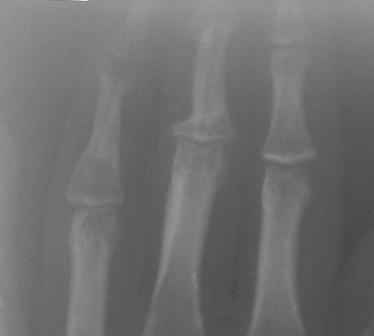

Re: Непонятный процесс в основной фаланге пальца

Уважаемый Юрий, действительно, онкологи делали пункционную биопсию.

Конечно, мы во время операции будем брать материал на гистологию, а также удаление очага и замещение аутотрансплантатом тоже в плане рассматривается, как на примере, которая была представлена на форуме. правда снимки не очень качественные, прощу извинения!